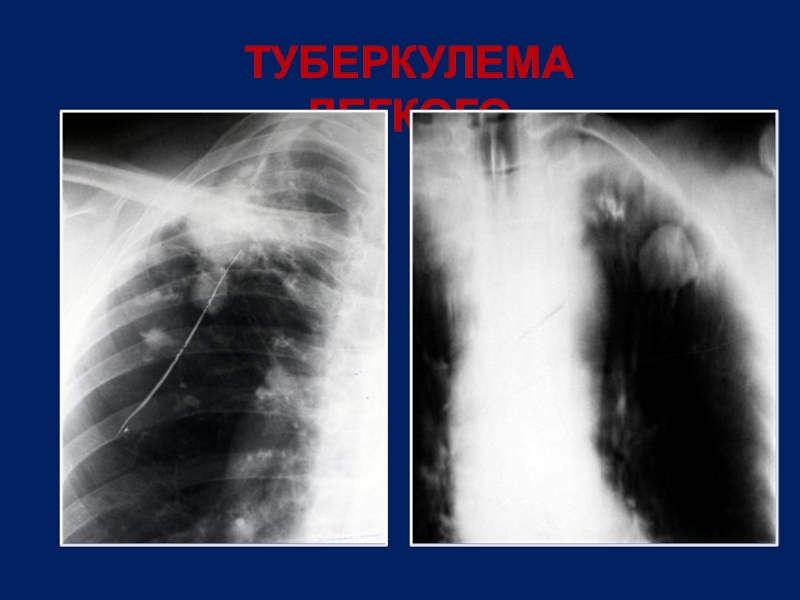

Слайд 10ТУБЕРКУЛЕМА ЛЕГКОГО

Rg –синдром – круглая тень

Локализация –

1, 2, 6 сегменты

Включения в виде кальцинатов

Распад в виде «серпа»

Наличие очагов отсева

Скудная клиническая симптоматика

МБТ в мокроте редко, при распаде

Реакции на туберкулин - выраженные

Слайд 11ТУБЕРКУЛЕМА ЛЕГКОГО

Слайд 12ТУБЕРКУЛЕМА ЛЕГКОГО